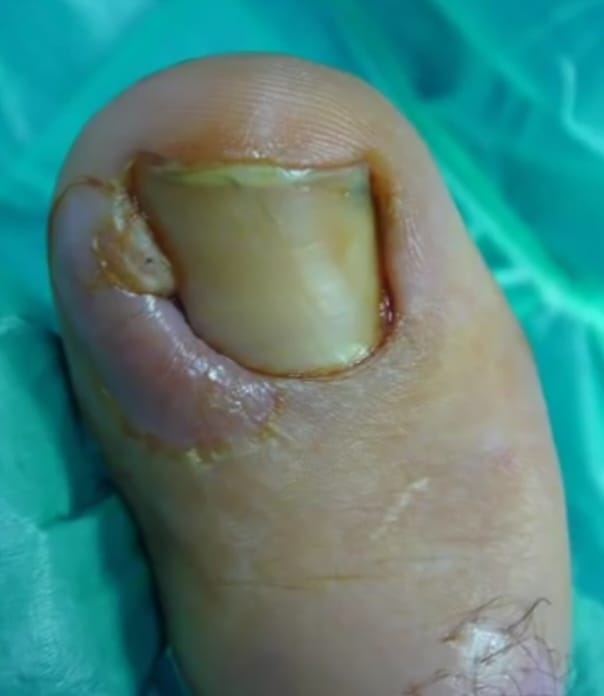

tratamiento de quiropodia en sevilla

Quiropodias: cuidado completo para tus pies en Sevilla

La quiropodia es un tratamiento esencial que abarca la eliminación de hiperqueratosis (durezas) y helomas (callosidades), así como la preparación, corte y fresado de uñas, tanto sanas como con cualquier tipo de alteración. En Centro Podológico Santa María del Trabajo, realizamos este tratamiento con la máxima precisión, complementándolo con una hidratación adecuada y un masaje relajante que mejora la circulación y alivia la tensión en tus pies.